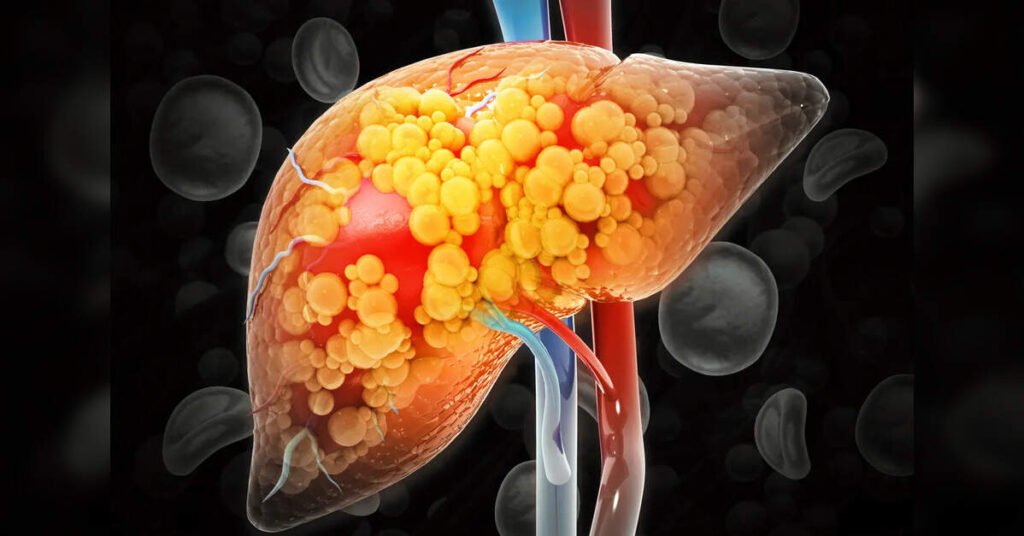

Hyderabad: A silent but rapidly growing health concern is emerging across urban India, with nearly one in three city residents estimated to have fatty liver disease, often without noticeable symptoms. On the occasion of World Liver Day, observed this year with the theme “Solid Habits, Strong Liver,” doctors warned that the condition, once associated largely with older adults, is now increasingly being diagnosed among individuals in the 30–50 age group.

Doctors say the most concerning aspect of fatty liver disease is its “silent” progression. In its early stages, the condition typically causes no symptoms and is often detected incidentally during routine medical tests. As a result, many patients seek care only when the disease has already progressed to serious complications such as cirrhosis or liver failure.